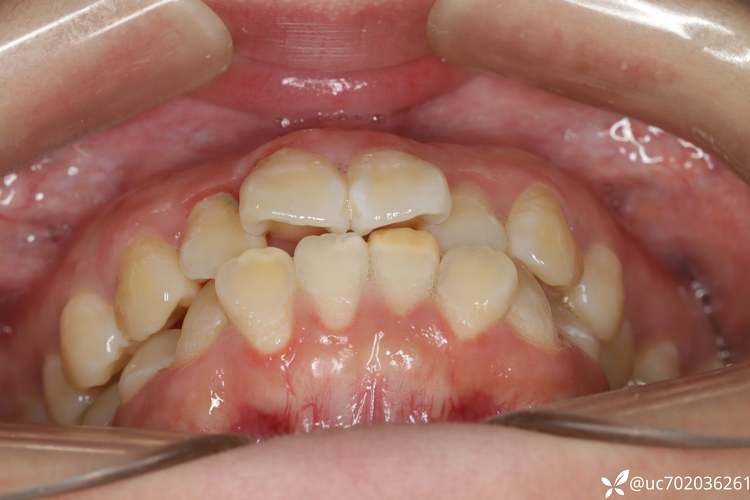

单侧牙齿严重拥挤

若患者一侧牙弓因骨量不足或牙量过大出现明显拥挤(如牙齿重叠、扭转),而另一侧相对整齐,仅通过磨牙或扩弓无法解决时,需在拥挤侧拔牙,为内收牙齿提供空间,左侧上下颌前磨牙区拥挤严重,右侧排列正常,可能选择拔除左上、左下第一前磨牙,利用拔牙间隙调整左侧牙弓形态,避免强行扩弓导致牙龈萎缩或面部凹陷。